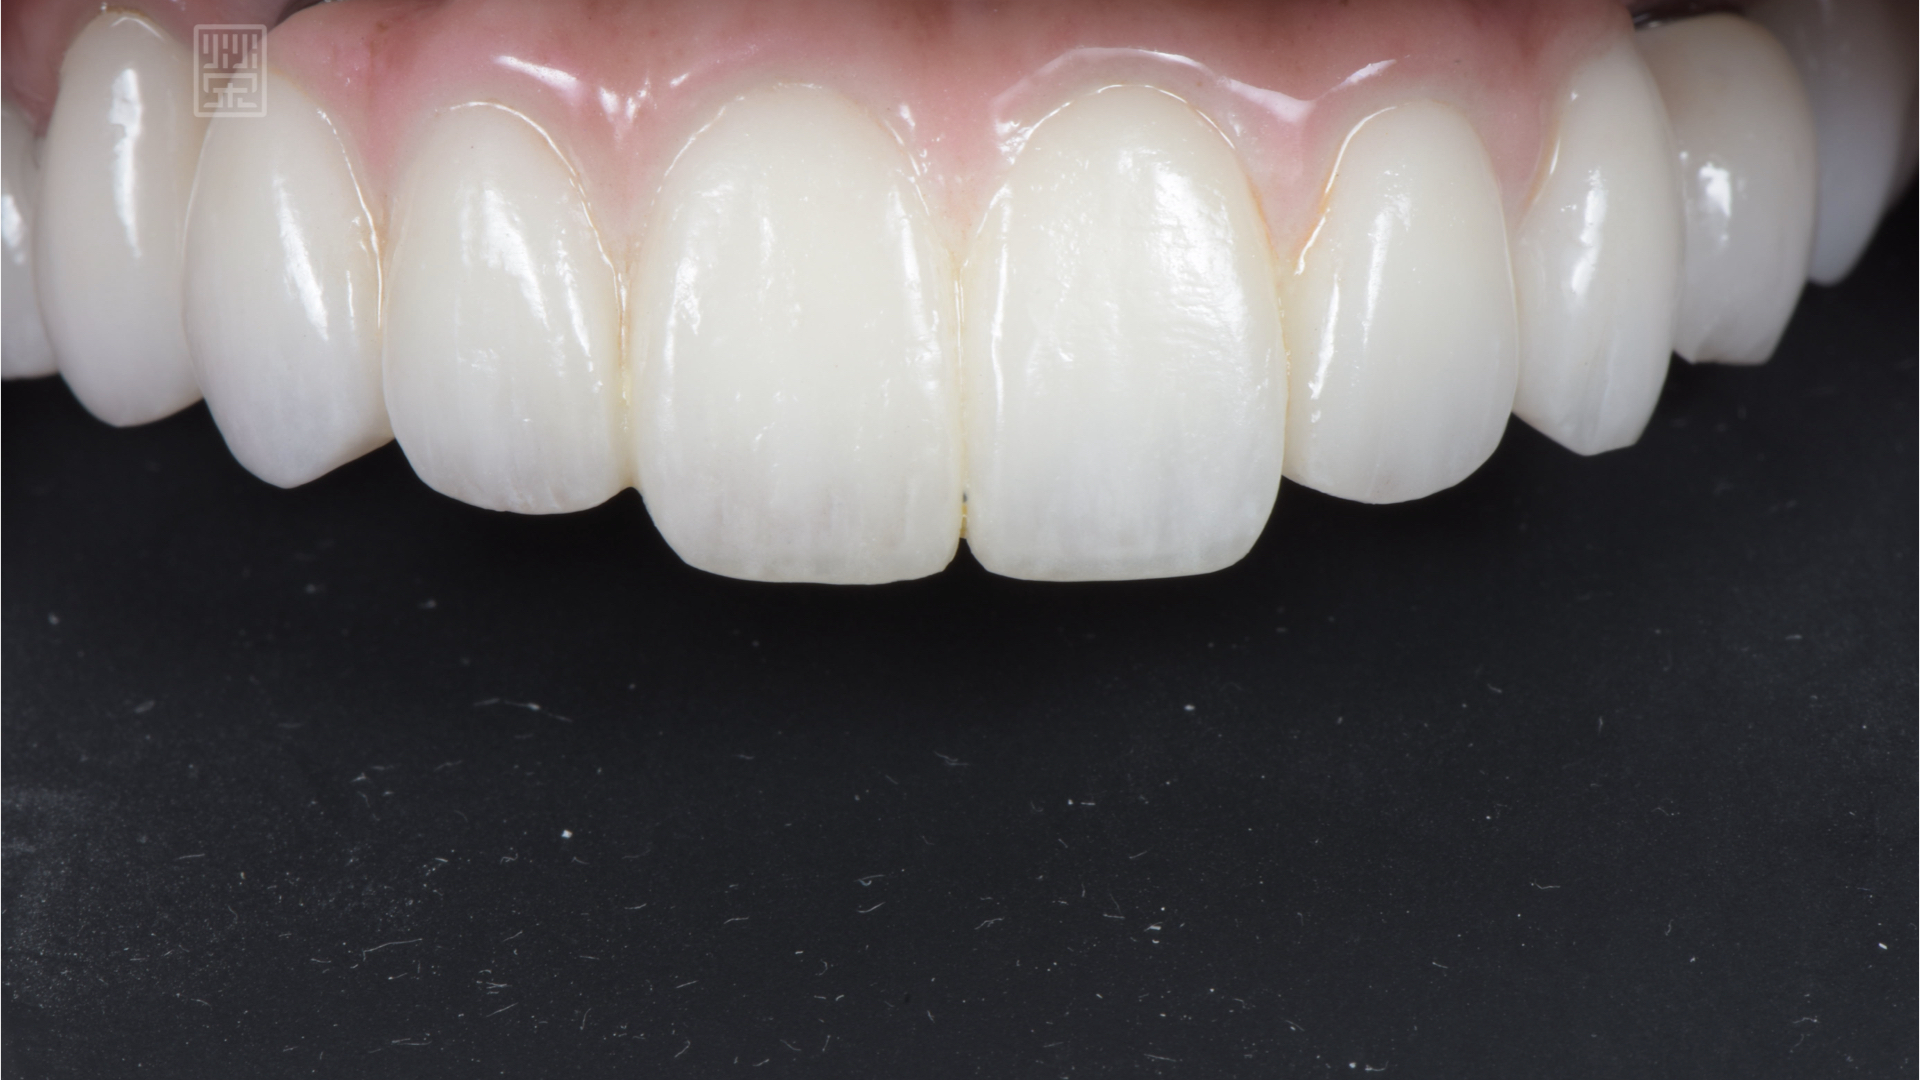

玻璃陶瓷貼片改變下顎門齒顏色與型態

全瓷贋復物完成

功能、型態、長度討論完後,蔡小姐更希望有一口白牙,所以除了植牙牙橋、假牙外,還希望將下顎牙齒用全瓷貼片包覆,改變原本齒色,除了改善齒色外,也將長期樹脂填補變色的問題改善。